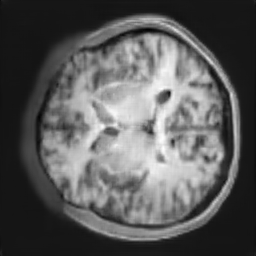

The study utilizes three 3D datasets, namely the GSP dataset[3], the LIDC-IDRI dataset[1], and the dataset employed for the Lung Nodule Analysis 2016 (LUNA16) challenge[21] which is a subset of LIDC-IDRI dataset. Samples from generated images at different stages of training are presented in Fig. 2 and Fig.3.

Figure 2: Synthetic images of CRF-GAN and HA-GAN at different iterations of training on GSP dataset